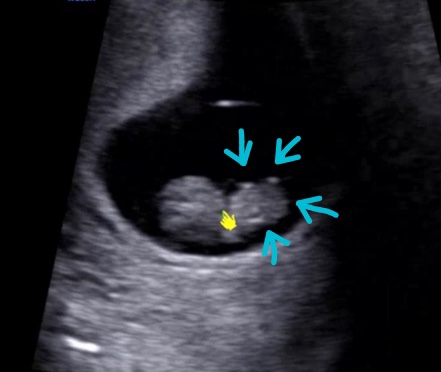

임신준비~임신 8주간의 기록 / 배테기사용법, 태아보험, 국민행복카드, 전주보건소 임산부 등록하기

요 게시판의 첫번째 글은 임신준비부터 임신확인, 그리고 8주차까지의 기록! 모든게 처음인지라,,, 나름 열...